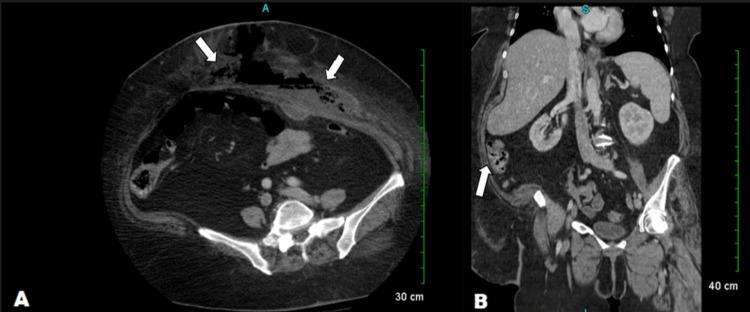

Necrotizing fasciitis (NF), commonly known as necrotizing soft tissue infection (NSTI), or flesh-eating disease is a rare but rapidly fatal aggressive bacterial infection of soft tissue and deep skin that results in the destruction of the underlying fascia. Symptoms include fever, tachycardia, hypotension, leukocytosis, pain, and large areas of red and swollen skin. Early diagnosis and aggressive management are compulsory for a better prognosis. In this case report, we present a 58-year-old obese woman who initially presented to the emergency department three weeks post-sleeve gastrectomy with hernia repair and was initially suspected of having a large, uncomplicated abdominal wall abscess. Several repeated drainages of the abdominal wall abscess and continued deterioration of the patient revealed foul-smelling, necrotic tissue and the subsequent diagnosis of NF. This case report highlights the importance of high clinical suspicion for NF and early, aggressive debridement and treatment to improve patient outcomes.

坏死性筋膜炎(NF),通常被称为坏死性软组织感染(NSTI)或噬肉病,是一种罕见但进展迅速、可致命的侵袭性软组织和深部皮肤细菌感染,会导致深层筋膜破坏。症状包括发热、心动过速、低血压、白细胞增多、疼痛以及大面积皮肤红肿。早期诊断和积极治疗对于改善预后至关重要。在本病例报告中,我们介绍了一名58岁的肥胖女性,她在袖状胃切除术后三周进行疝修补时最初就诊于急诊科,最初被怀疑患有一个较大的、无并发症的腹壁脓肿。对腹壁脓肿进行多次反复引流以及患者病情持续恶化后,发现有恶臭的坏死组织,随后诊断为坏死性筋膜炎。本病例报告强调了对坏死性筋膜炎保持高度临床怀疑以及早期积极清创和治疗以改善患者预后的重要性。